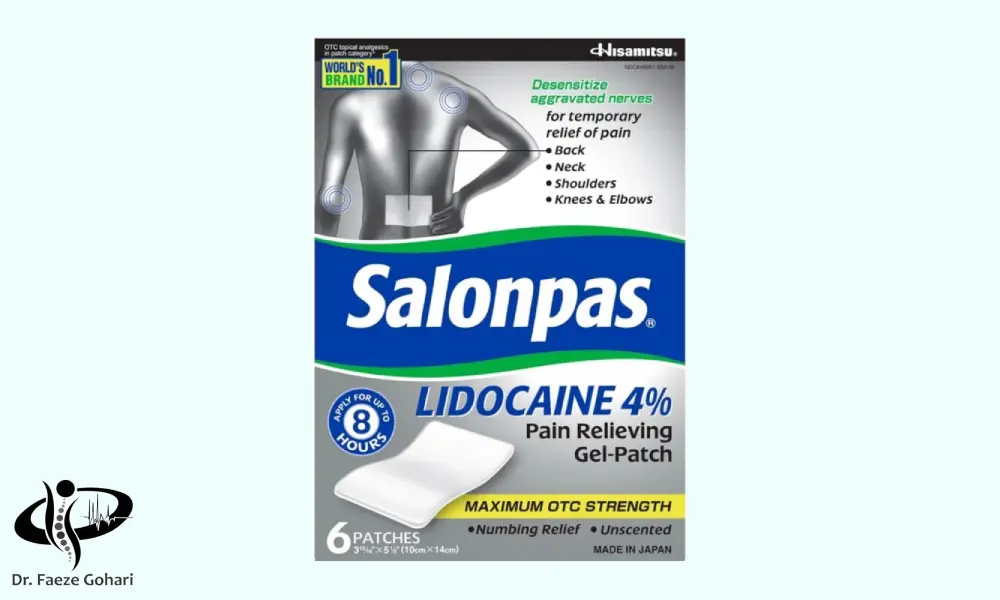

استفاده از چسبهای ضد درد

چسبهای ضد درد حاوی داروهای ضددرد مانند لیدوکائین یا ترکیباتی مانند منتول هستند که بهصورت موضعی بر ناحیه دردناک اعمال میشوند. در کمردردهای التهابی، این چسبها با نفوذ دارو از طریق پوست به بافتهای زیرین، التهاب را به صورت موقت کاهش داده، درد را تسکین میدهند و بدون عبور از دستگاه گوارش، عوارض کمتری نسبت به مصرف خوراکی ایجاد میکنند. همچنین به دلیل آزادسازی تدریجی ماده مؤثر، اثر آرامبخشی مداومتری دارند و گزینهای مناسب برای دردهای مزمن و متمرکز در ناحیه خاصی از کمر محسوب میشوند.

نمونهای از چسبهای ضد درد موجود در داروخانهها

نمونهای از چسبهای ضد درد موجود در داروخانهها

برای تهیه این چسبها، در داروخانه میتوانید درخواست چسبها یا پچهای ضد درد را داشته باشید که بسته به نوع، حاوی داروی ضدالتهاب یا ترکیبات گیاهی مسکن هستند. پیش از چسباندن، پوست محل باید تمیز و خشک باشد. چسب را دقیقاً روی محل درد بچسبانید و اجازه دهید ۸ تا ۱۲ ساعت روی پوست بماند (بسته به نوع محصول). بهتر است بیش از یک بار در روز استفاده نشود، مگر با تجویز پزشک. در صورت بروز قرمزی، خارش یا حساسیت پوستی، مصرف قطع شود. از چسباندن همزمان چند پچ یا استفاده همزمان با پمادهای موضعی پرهیز شود.